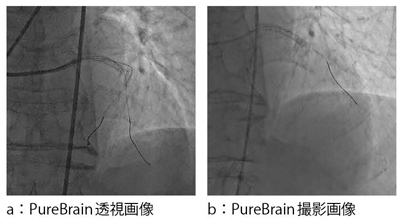

残像については,図4に示すように,回転ファントムによって,従来型のリカーシブフィルタ方式に比べ大幅に低減していることが認められる。このPureBrainによって得られる透視画像と撮影画像の一例を図5に示す。透視で残像がほとんど出ないため,透視画像でもガイドワイヤーを鮮明に確認することができる。

図5 PureBrainの一例